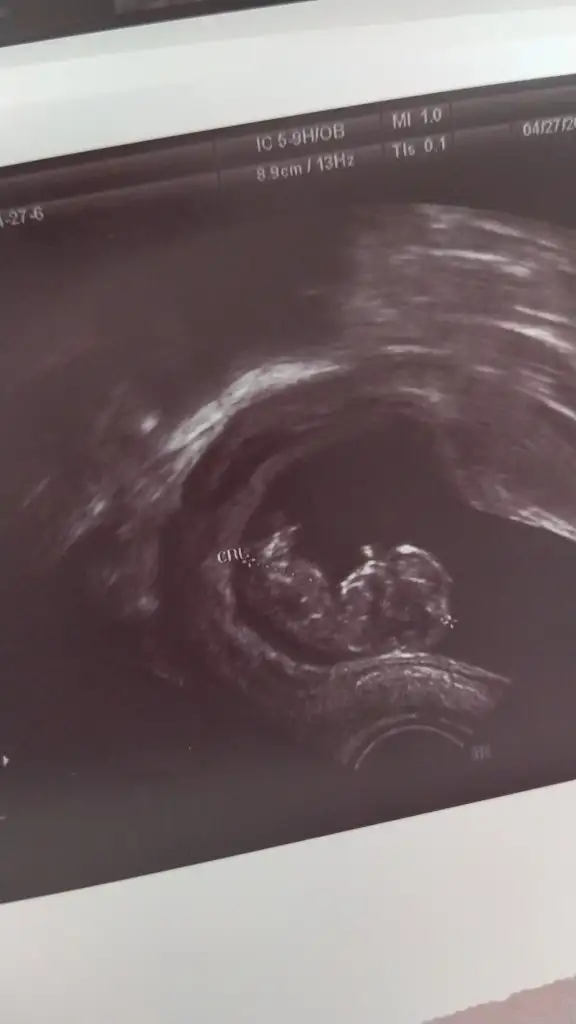

Yaa banada bakarmisiniz 10+3 vajinal bakıldı bugün 🙏🥰

• IMG-20220427-WA0038.webp

IMG-20220427-WA0038.webp

11,4 KB · Görüntüleme: 94